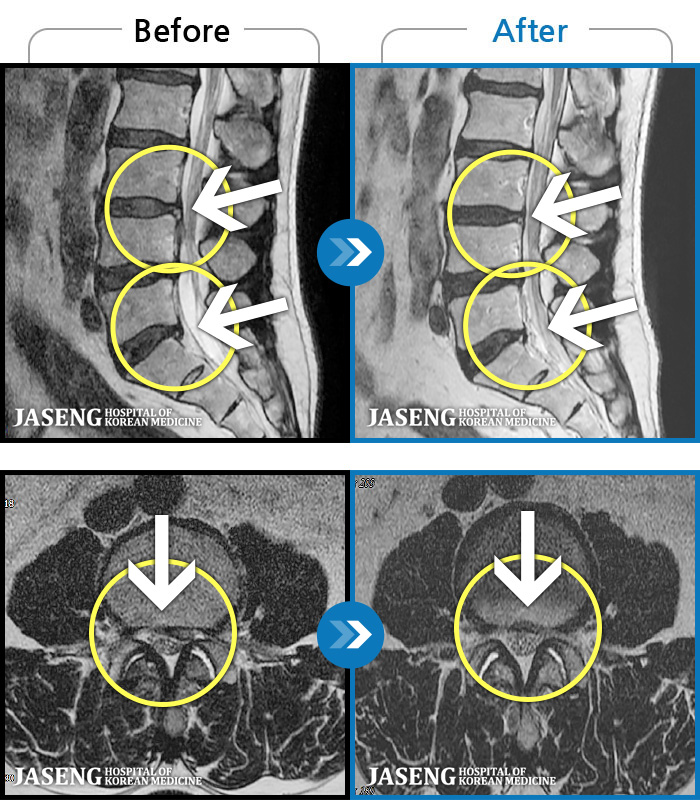

허리디스크

인천 · 강아현 원장

우측 허리 통증 및 다리 저림이 심하여 앉거나 바로 눕는 것도 힘든 상태로 내원하셨습니다. 감각 저하도 동반되어 심각한 신경손상이 의심되는 상황이었습니다.

촬영시기

2024.07.27 ~ 2025.04.05

2025.04.16

조회수 350